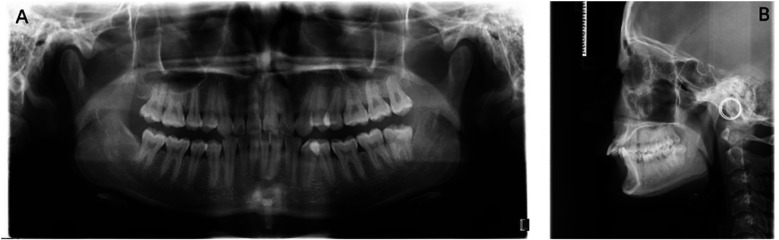

牙根吸收是正畸治疗后的主要并发症之一。这是一种涉及缺血性坏死的炎症过程。因此,它被称为正畸诱导炎症根吸收(OIIRR)。本报告的目的是提出一个病例研究的患者在她的20谁经历了内根吸收在两个上颌中门牙的正畸治疗的结果。将三氧化二矿聚集体(mta)应用于根吸收损伤以促进再矿化。经过3年的随访,临床和影像学检查显示未发现与吸收性病变相关的透光度,无任何病理症状。

Root resorption is one of the leading complications that follows orthodontic treatment. It's an inflammatory process involving ischemic necrosis. Therefore, it is called orthodontically induced inflammatory root resorption (OIIRR). The purpose of this report is to present a case study of a patient in her 20s who experienced internal root resorption on two maxillary central incisors as a result of orthodontic treatment. Mineral trioxide aggregates (MTAs) were applied to the root resorption lesion to promote remineralization. A clinical and radiographic examination revealed that no radiolucency related to the resorptive lesion was found without any pathological symptoms after a 3-year follow-up.